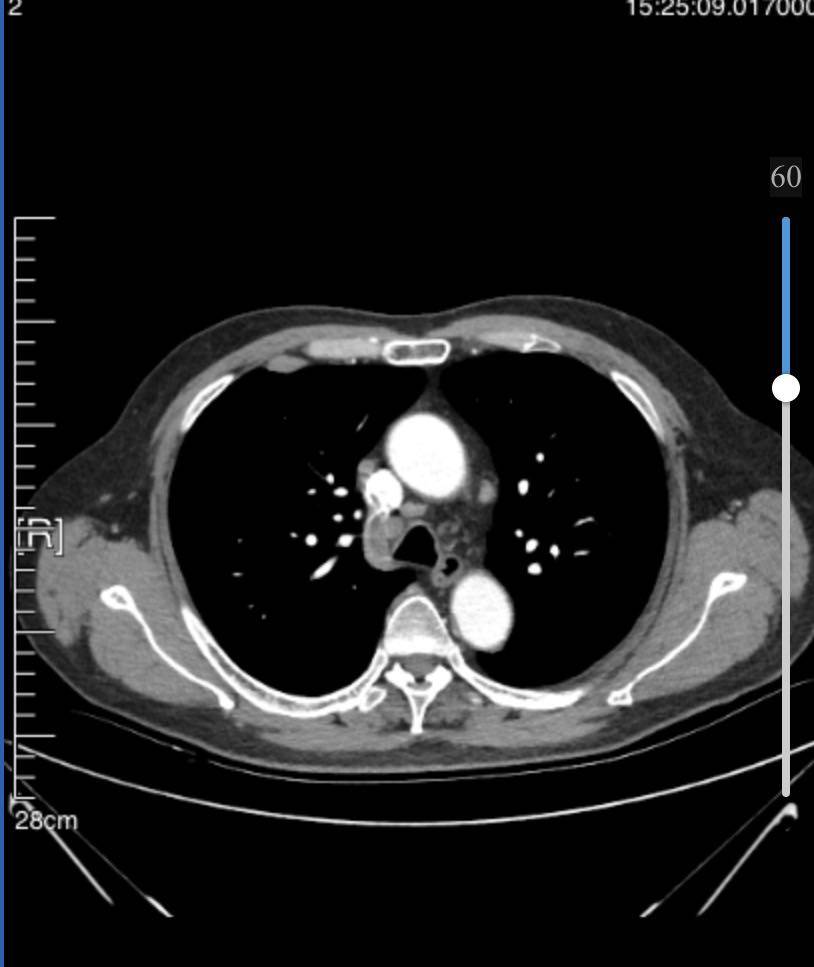

8月21日胸ct显示右肺下叶占位,3.4cm*3.0cm,纵隔及右肺门多发增大淋巴结;右前肋胸膜外脂肪间隙内淋巴结肿大;左肺上叶磨玻璃结节1.6cm,微浸润性腺ca。

后来我去北大肿瘤,肿瘤内科专家首先指出我们没有做patct 又指出左侧淋巴结也有增大,这个左侧的淋巴结,我之前是完全不知道的。后来学习到网上关于分期,才知道我父亲现在属于3a和3b的临界,左侧这个不知道是不是,医生也判断不明确,但做手术预后也怕不好。我现在真的不知道怎么办了。父亲的事情都需要我来做决定,压力好大…

目前已经服药1个月,10月23号拍ct,右下肿瘤2.4*2.5,淋巴结略有缩小,磨玻璃结节1.4…